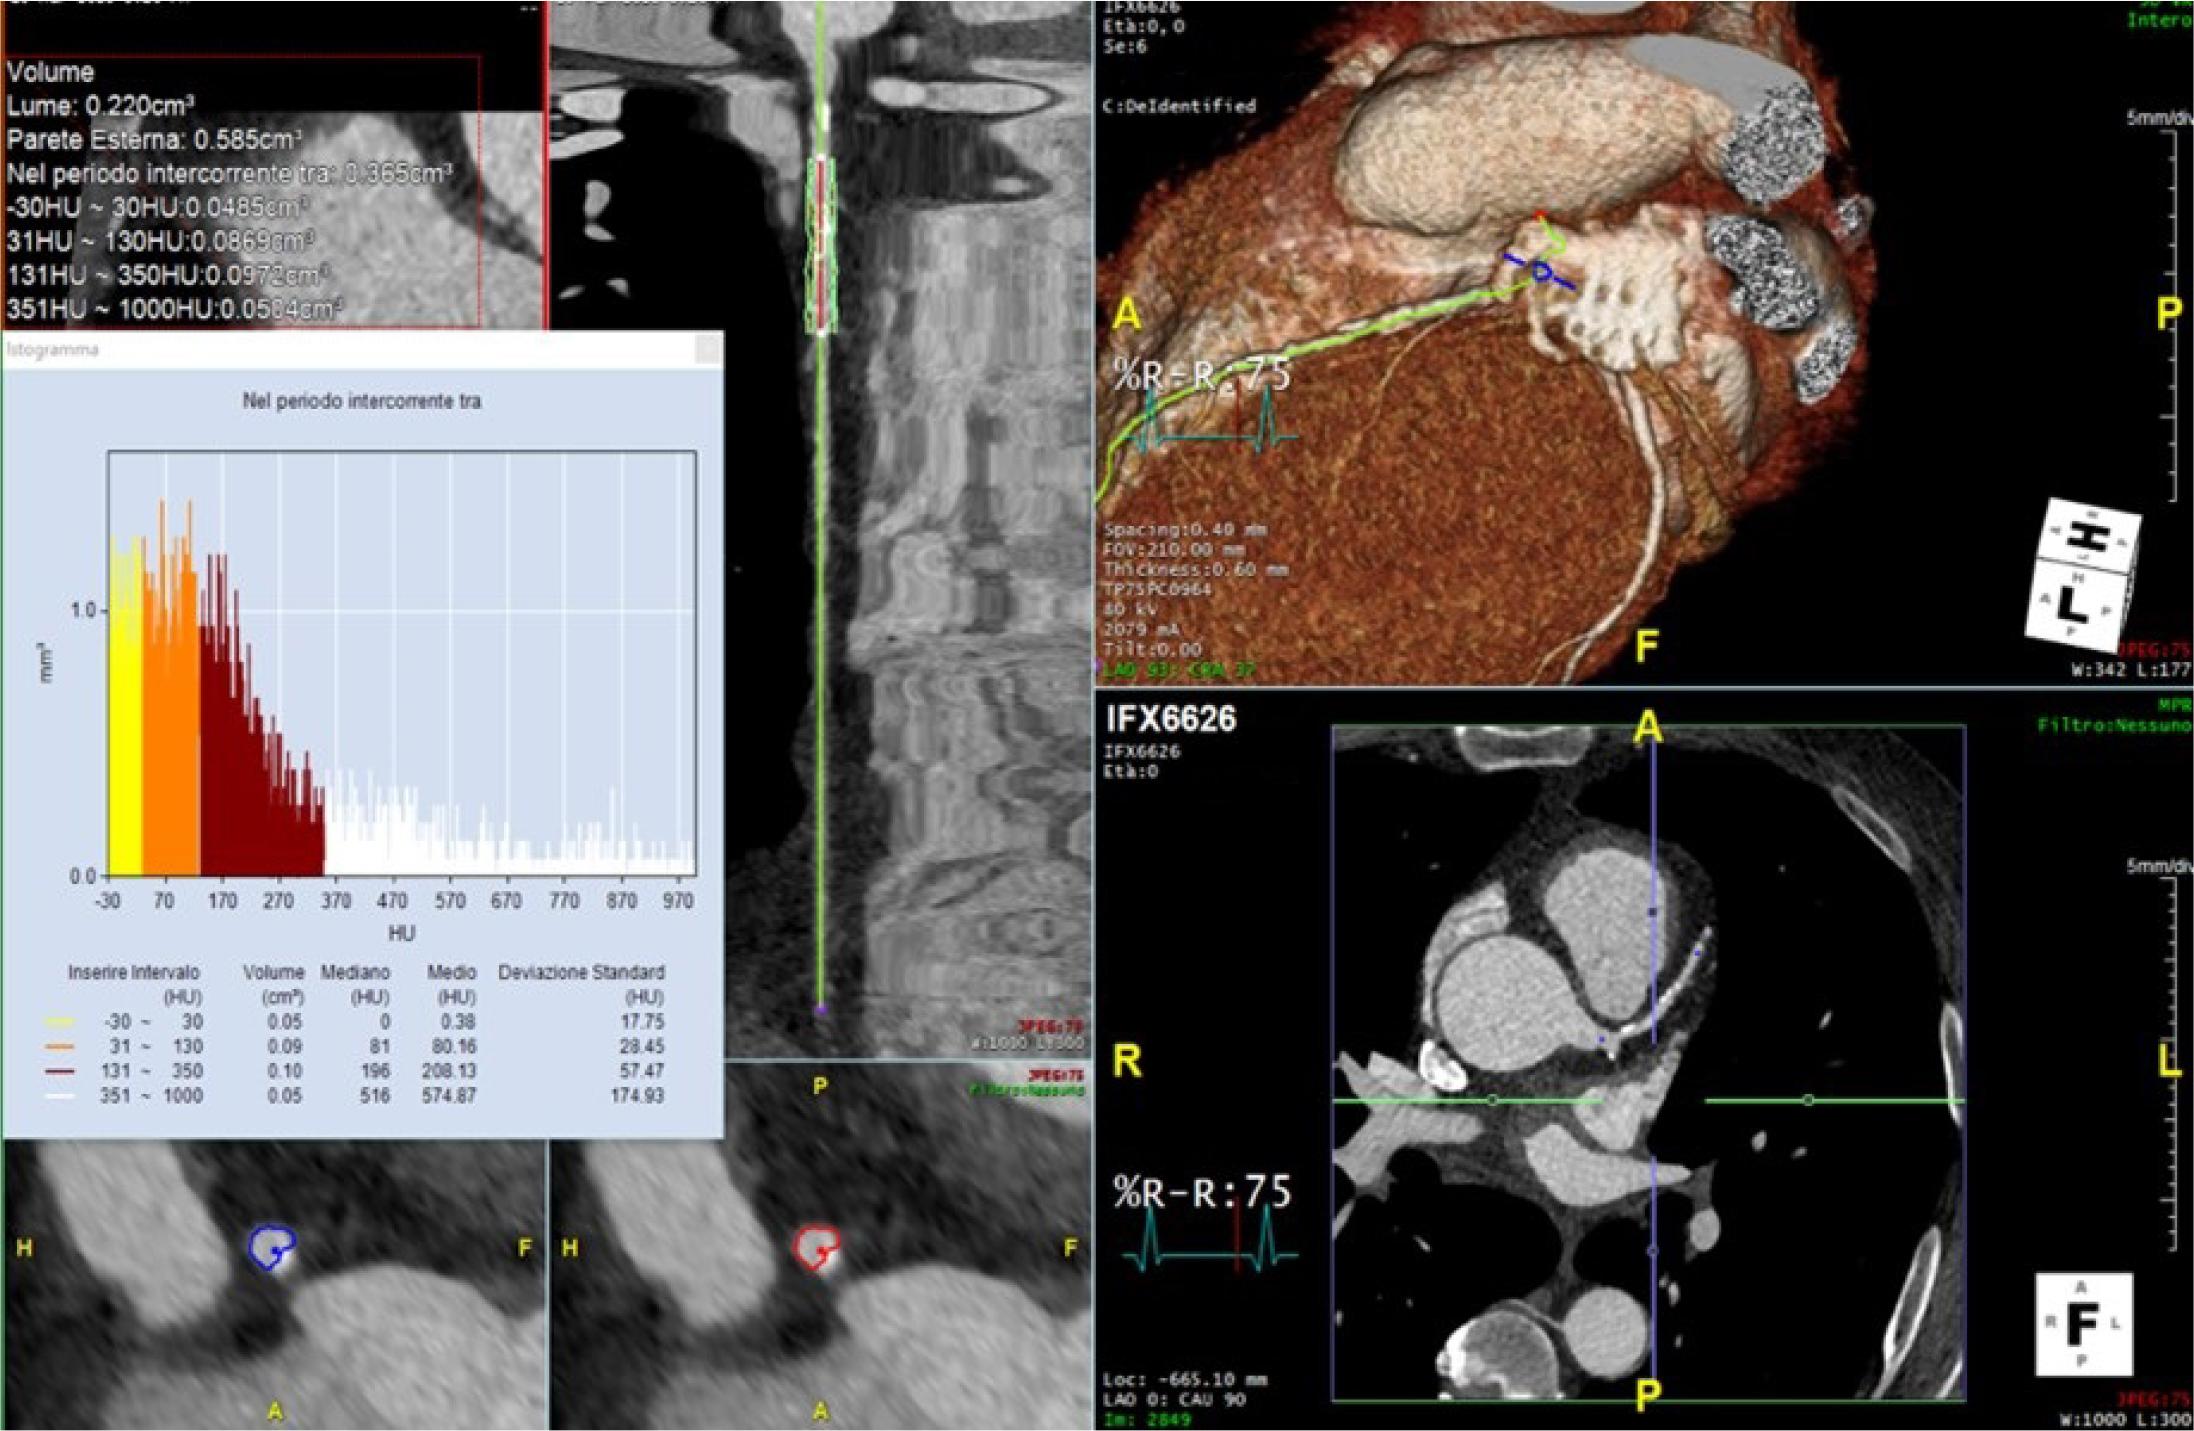

| Low Attenuation Plaque | Low density (<30 HU) | Associated with increased risk of rupture |